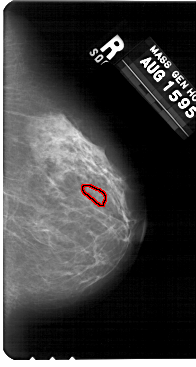

ics_version 1.0 filename A-1310-1 DATE_OF_STUDY 15 8 1995 PATIENT_AGE 48 FILM FILM_TYPE REGULAR DENSITY 1 DATE_DIGITIZED 7 7 1998 DIGITIZER HOWTEK 43.5 SEQUENCE LEFT_CC LINES 5491 PIXELS_PER_LINE 2851 BITS_PER_PIXEL 12 RESOLUTION 43.5 NON_OVERLAY LEFT_MLO LINES 5491 PIXELS_PER_LINE 3166 BITS_PER_PIXEL 12 RESOLUTION 43.5 NON_OVERLAY RIGHT_CC LINES 5491 PIXELS_PER_LINE 2926 BITS_PER_PIXEL 12 RESOLUTION 43.5 OVERLAY RIGHT_MLO LINES 5491 PIXELS_PER_LINE 2956 BITS_PER_PIXEL 12 RESOLUTION 43.5 OVERLAY |

FILE: A_1310_1.RIGHT_MLO.OVERLAY TOTAL_ABNORMALITIES 1 ABNORMALITY 1 LESION_TYPE CALCIFICATION TYPE PLEOMORPHIC DISTRIBUTION CLUSTERED ASSESSMENT 4 SUBTLETY 1 PATHOLOGY BENIGN TOTAL_OUTLINES 1 BOUNDARY |